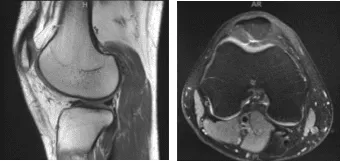

MRI-3T Right knee Non-contrast

On his MRI results it showed trace joint effusion and minimal patellar chondromalacia. Unremarkable MRI examination of the right knee.